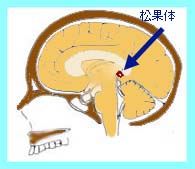

���ʑ�

���ʑ̂ł��B�]�̐[���ɂ���܂��B

���ʑ̂Ɏ�ᇂ̂������W���[�~�m�[�}�̈��ł��B

�����̐}�ŏ��ʑ̕��Ɏ�ᇂ��݂��܂��B